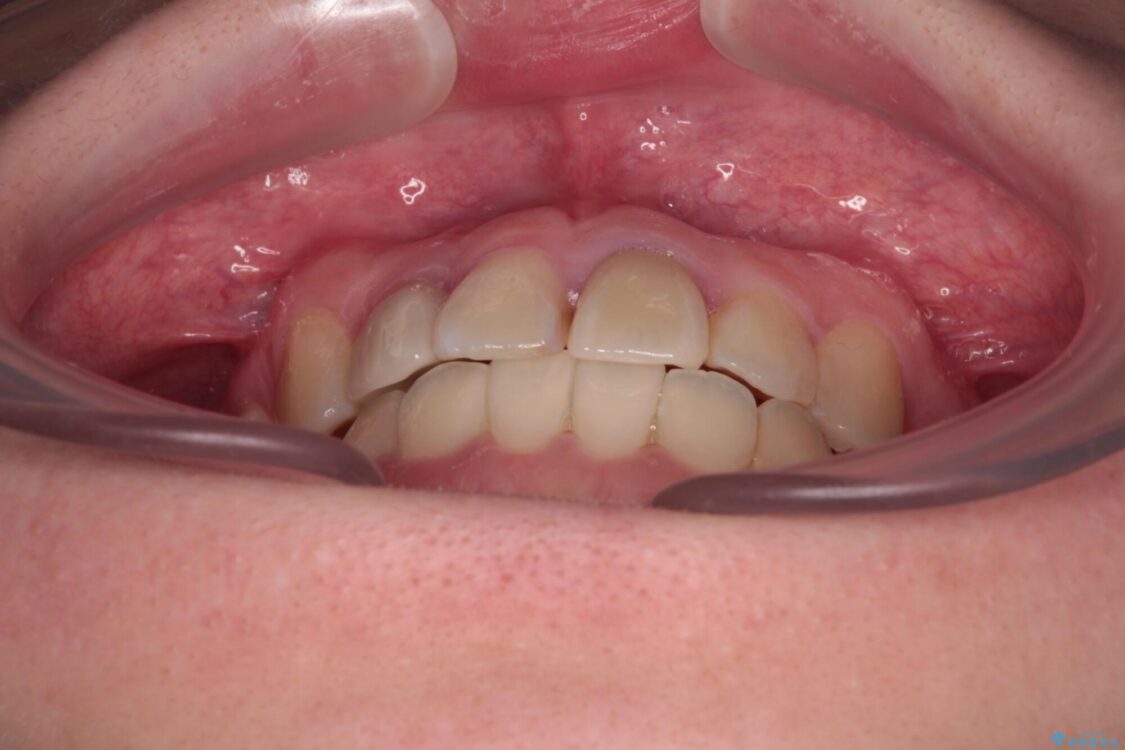

治療途中

• 虫歯治療ついでに歯並びの後戻りを改善 インビザラインによる矯正治療 治療途中画像